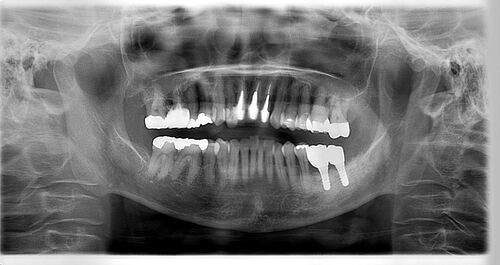

インプラント治療の症例2

レントゲン写真

- Befor

- After

| 年齢 | 50代・男性 |

| 主訴 | 左上7番 左下5番7番 |

| 治療内容 | ・インプラント埋入 ※1:GBR(骨造成)・・・骨再生誘導法。骨の高さや厚みを人工骨や人工膜などを使用し再生する方法 |

| 治療費 | 合計:1,809,500円(税込) ■内訳 ・左上7番 ・左下5番7番 |

| 治療期間 | 左上7番約1年 左下5番7番約10ヵ月 |

| 治療方針 | 左上7番は昔他院で被せものをしており、被せものの中が歯ぐきの中まで虫歯になっていたため抜歯せざるを得ない状態だった。抜歯と同時に骨造成を行い、骨が出来るまで4ヵ月待ってからインプラントを埋入した。 ※2ポンティック・・・歯のない部分を補うダミーの歯。 |

| 担当者所見 | 元々金属の被せものが多く入っていたため、2次カリエス※3が多かった。今回は金属ではなく、ジルコニアを使用し、2次カリエスにならないよう、患者様にはブラッシング指導とメンテナンスの重要性をお伝えした。 ※3二次カリエス・・・詰め物や被せものを入れた歯が虫歯になること。 |